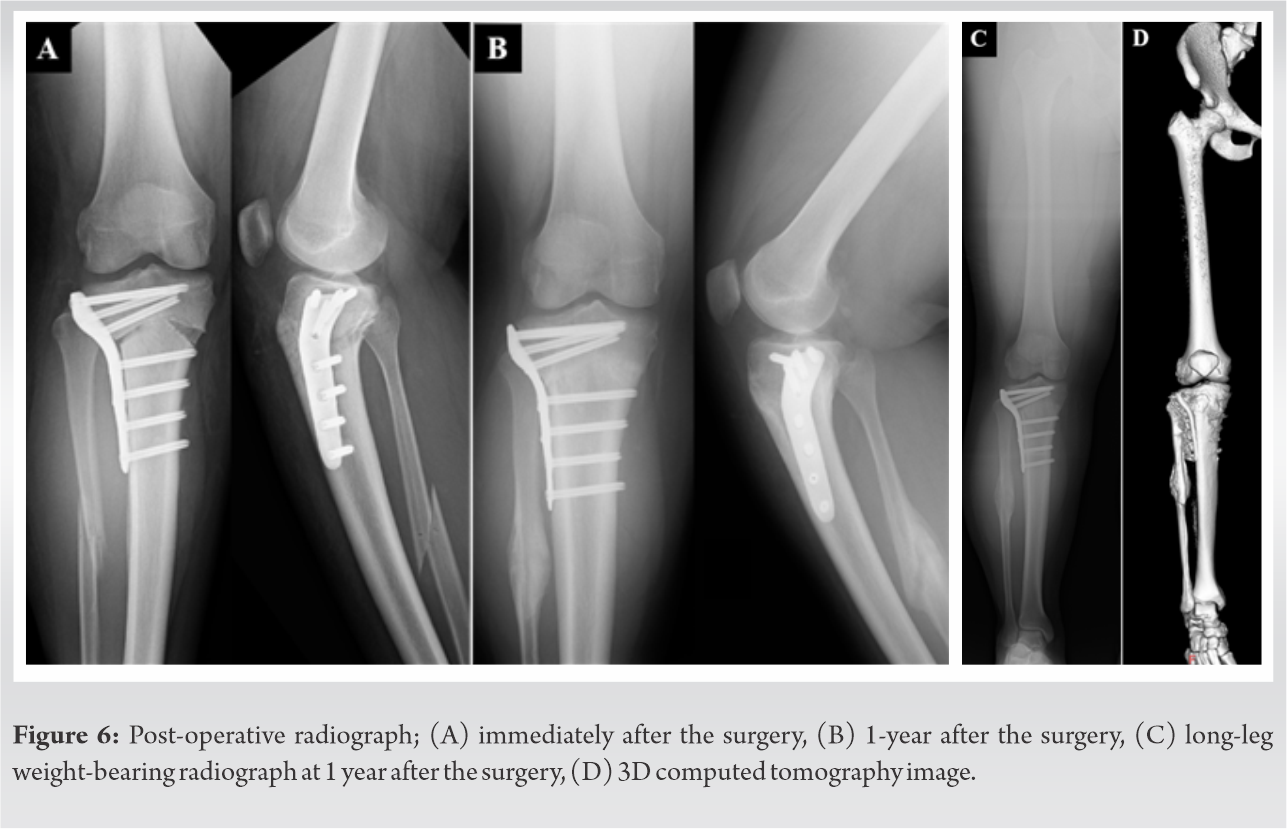

Continuous passive ROM was started one 1 day after the surgery, and the patient was allowed to bear only one-sixth of the body weight (BW) at 1-week post-surgery, each one-sixth of the BW was additionally loaded week by week. The patient was permitted to resume his sports activities gradually 3 months postoperatively. The patient finally resumed his daily activities and could perform quite well at sports as well at 1-year post-surgery (Supplemental File 2). Post-operative MPTA was 95°, FTA was 177°, and WBLR was 35% (Fig. 6A-C). Post-operative 3D-CT imaging revealed that the bones had united completely (Fig. 6D). The subscales of post-operative KOOS also improved to 96.43, 97.22, 100, 100, and 100, respectively.